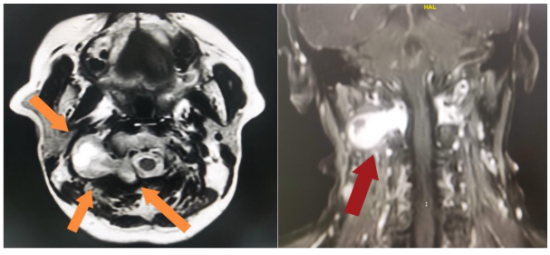

患者因头颈部疼痛持续两年来到哈医大一院就诊,经检查确诊为寰椎与枢椎间哑铃形椎管内外沟通性肿瘤,大小约4.5厘米。上颈椎区域解剖结构复杂,脊髓掌控颈部以下运动、感觉及大小便、呼吸功能,被医学界公认为“生命禁区”;且肿瘤跨越椎管内外,内侧压迫脊髓、外侧紧邻椎动脉,术中稍有不慎便可能导致四肢瘫或致命性出血。传统手术还需大面积剥离椎旁肌肉、咬除骨质,易破坏颈椎稳定性,术后常出现颈部僵硬、肌肉萎缩等并发症。

图1:术前影像检查提示肿瘤位于上颈椎颈1-2之间,椎管内外沟通肿瘤